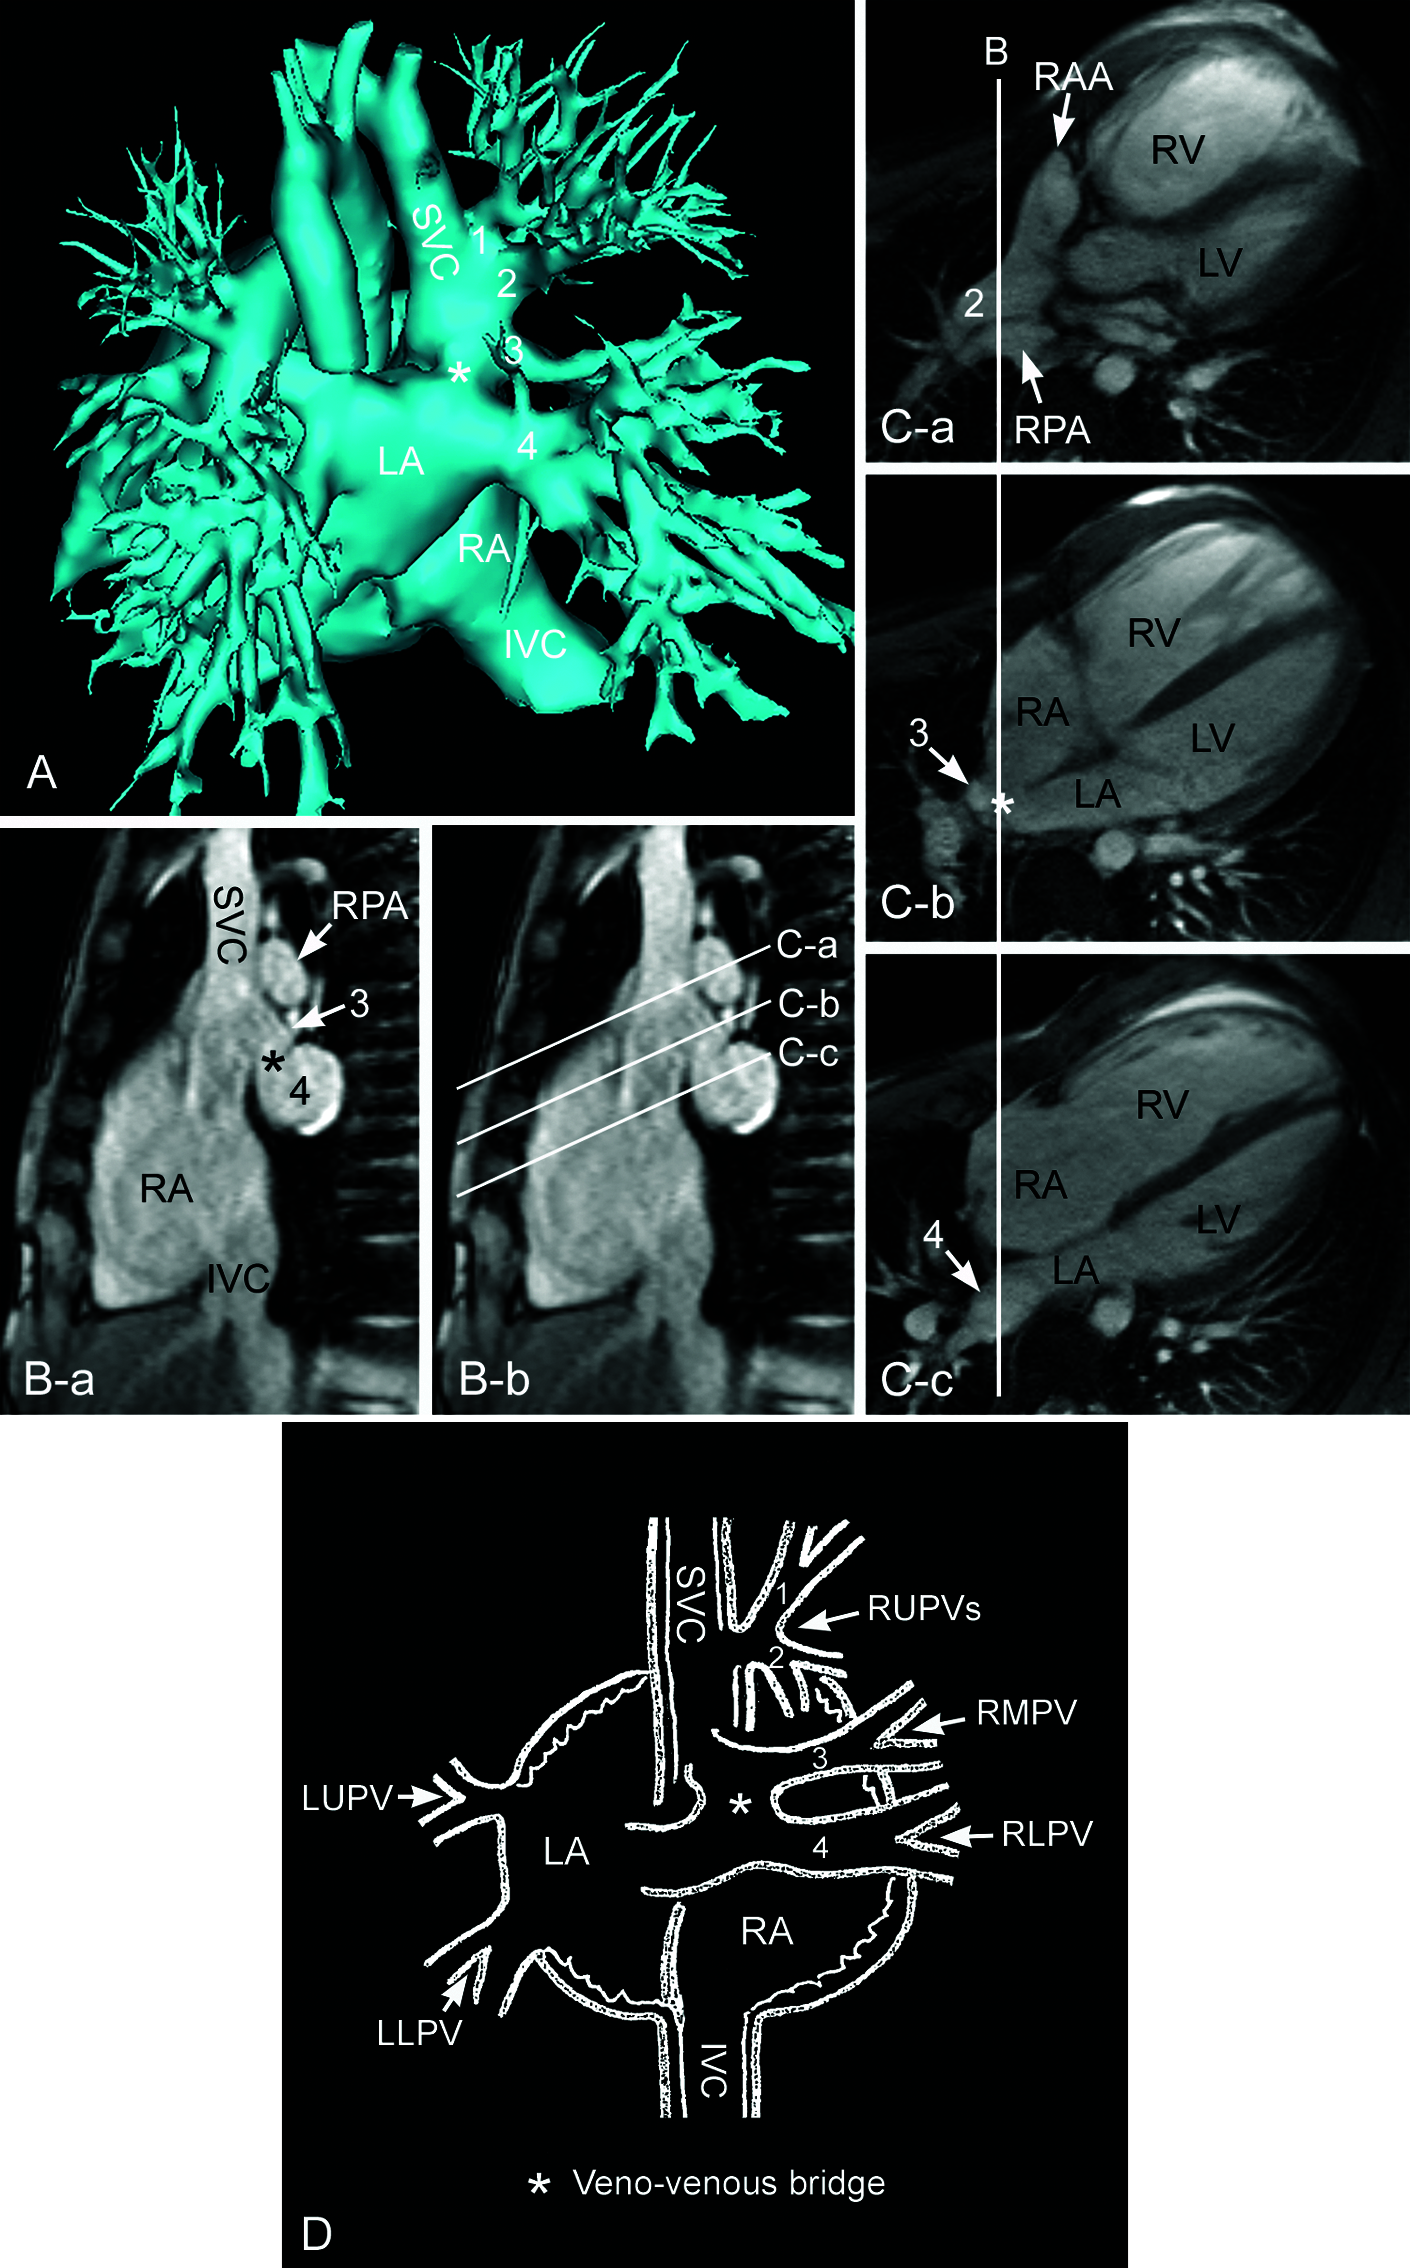

Figure 10: Magnetic resonance images showing superior sinus venosus defect with so-called veno-venous bridge. A. Volume rendered contrast enhanced angiogram. B. Static intercaval or bicaval image. C. Still frames of cine imaging along the planes shown in B. D. Cartoon showing veno-venous bridge. Two pulmonary veins (1 and 2) from the right upper lung connect to the lateral wall of the lower superior vena cava (SVC). Another small pulmonary vein (3) from the right middle lung connects to the posterior lateral wall of the junction between the superior vena cava and the right atrium (RA), forming a small pouch-like space. This small pouch communicates with the large right lower pulmonary vein (4) at its connection to the left atrium (LA) through a defect (asterisk) that can be called a bridge between the right middle and lower pulmonary veins. IVC, inferior vena cava; LLPV, left lower pulmonary vein; LUPV, left upper pulmonary vein; RAA, right atrial appendage; RLPV, right lower pulmonary vein; RMPV, right middle pulmonary vein; RPA, right pulmonary artery; RUPV, right upper pulmonary vein

Infrequently, the interatrial communication is indirectly through the defect between the pulmonary vein that is abnormally connected to the superior vena cava and the right lower pulmonary vein that is connected to the left atrium (Fig. 10). Butts et al. coined the term “veno-venous bridge” for this unique feature [9,18].